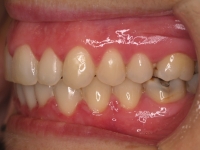

Premolar mandibular incluido + fenestración

45 incluido